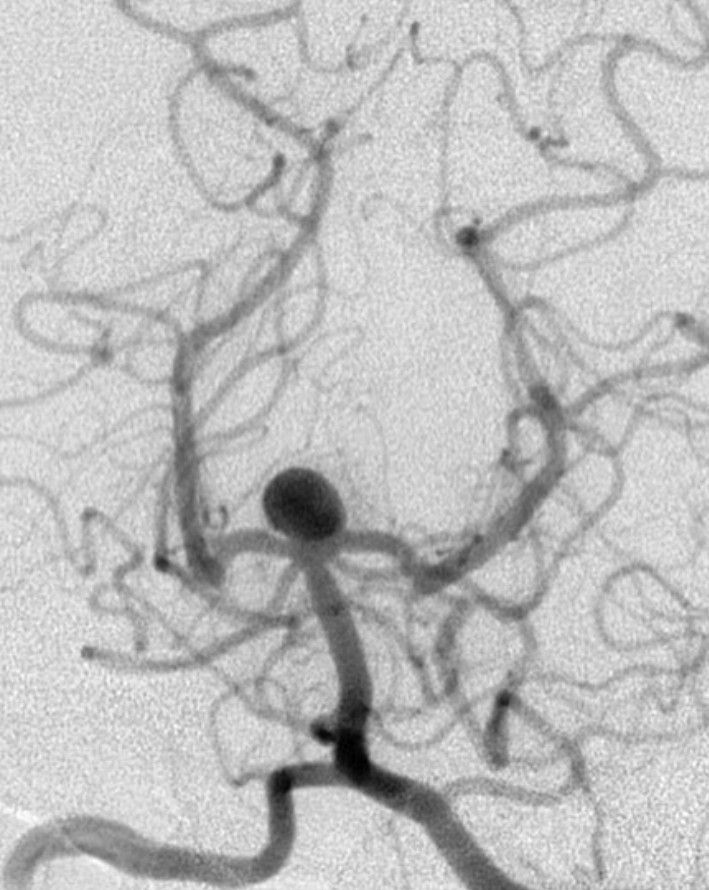

A berry aneurysm, which looks like a berry on a narrow stem, is the most common type of brain aneurysm. They make up 90 percent of all brain aneurysms, according to Stanford Health Care. Berry aneurysms tend to appear at the base of the brain where the major blood vessels meet, also known as the Circle of Willis.